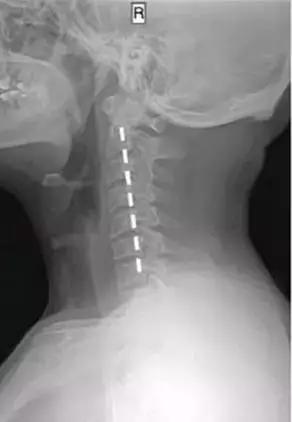

正常的颈椎有一个c型的生理弧线,他能保证颈椎的灵活性和稳定性,也正是这个弧线,使7块颈椎小骨头可以承受整个头部的重量。

当颈椎曲度变直甚至反弓,这个完美的弧线不存在了,会造成颈椎退行性改变,椎间盘突出,造成神经卡压、头痛、头晕。

检查方法:通过x光检查区分,是否存在颈椎曲度变直,颈椎间盘突出压迫神经,造成神经卡压。